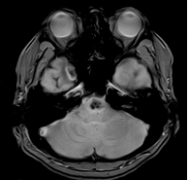

鞍内脑海绵状血管瘤案例,颅内出血在磁共振成像(MRI)上具有特征性表现,包括T1加权像上的等强度、T2加权像上的高强度和鞍区钆增强T1加权像上的弥散均匀强化。在这篇报告中,我们提...